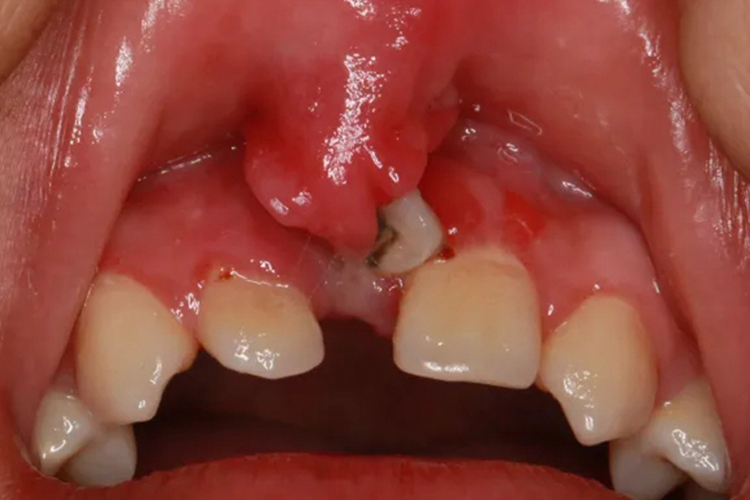

上嘴唇小筋上长了个肉芽,可表现为上唇系带的丘疹、肉芽肿、乳头瘤样疣体等。

上嘴唇小筋应指上唇系带,长了个肉芽可能由扁平苔藓、结节病、尖锐湿疣等导致。

尖锐湿疣的口腔表现为小而柔软的粉红色丘疹,针帽或米粒大,逐渐增大至长锥形疣状物,可单发或数量逐渐增多,表面高低不平,质地柔软。如不及时治疗,疣体将逐渐增大,成为大的菜花状或乳头瘤样、鸡冠样的赘生物,基底有蒂;有的彼此融合,表面亦可角化发白或有糜烂、溃疡,有分泌物。患者一般无自觉症状,病变多好发于舌、腭、唇、颊及牙龈。患者无痛,可有异物感。